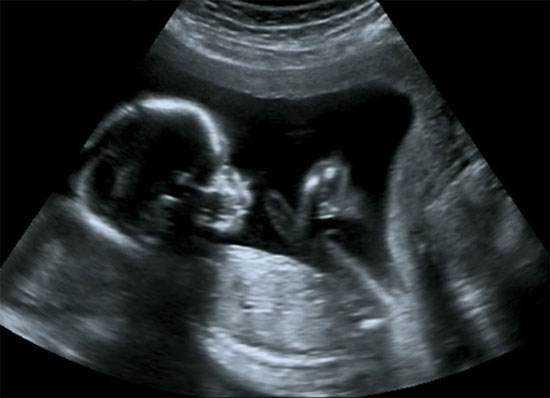

B超检查既能对胎盘定位、羊水测量,又能对单胎多胎、胎儿发育情况及有否畸形和葡萄胎等作出早期诊断。

整个孕期差不多有7次以上的B超检查,而B超单上的各种数据都代表着胎宝宝的实际状况,那么为什么还是不能准确查出宝宝的残疾呢?

可事实上,除了基因变异性的疾病,还有很多疾病是B超检查不出来的。